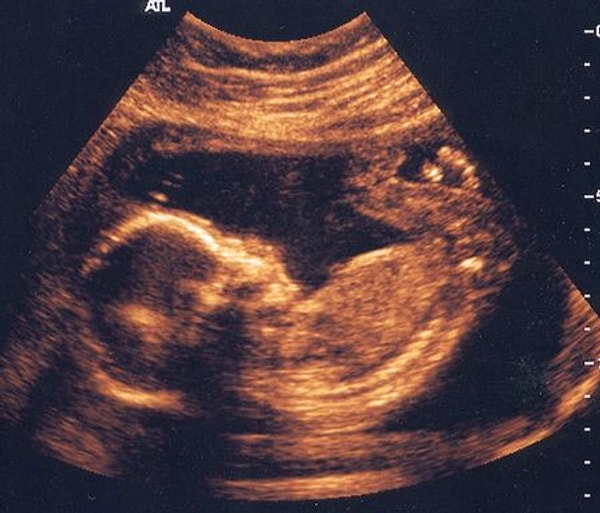

17. Этап развития лица малыша.